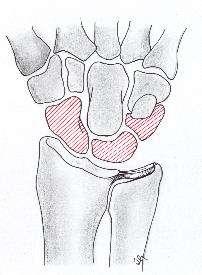

치료 중에 IIIB 부터 시행하는 치료는 아래와 같습니다.

Stage III 부터는 주상골도 영향을 받기 시작하며 회전을 하거나(IIIA, cortical ring 관찰가능), carpal height 가 줄어드는 것을 확인할 수 있습니다. (IIIB), IIIA 까지는 II와 치료를 거의 동일하게 하지만, IIIB 부터는 Proximal row carpectomy 나 STT, SC fusion 등을 시행해 볼 수 있습니다.